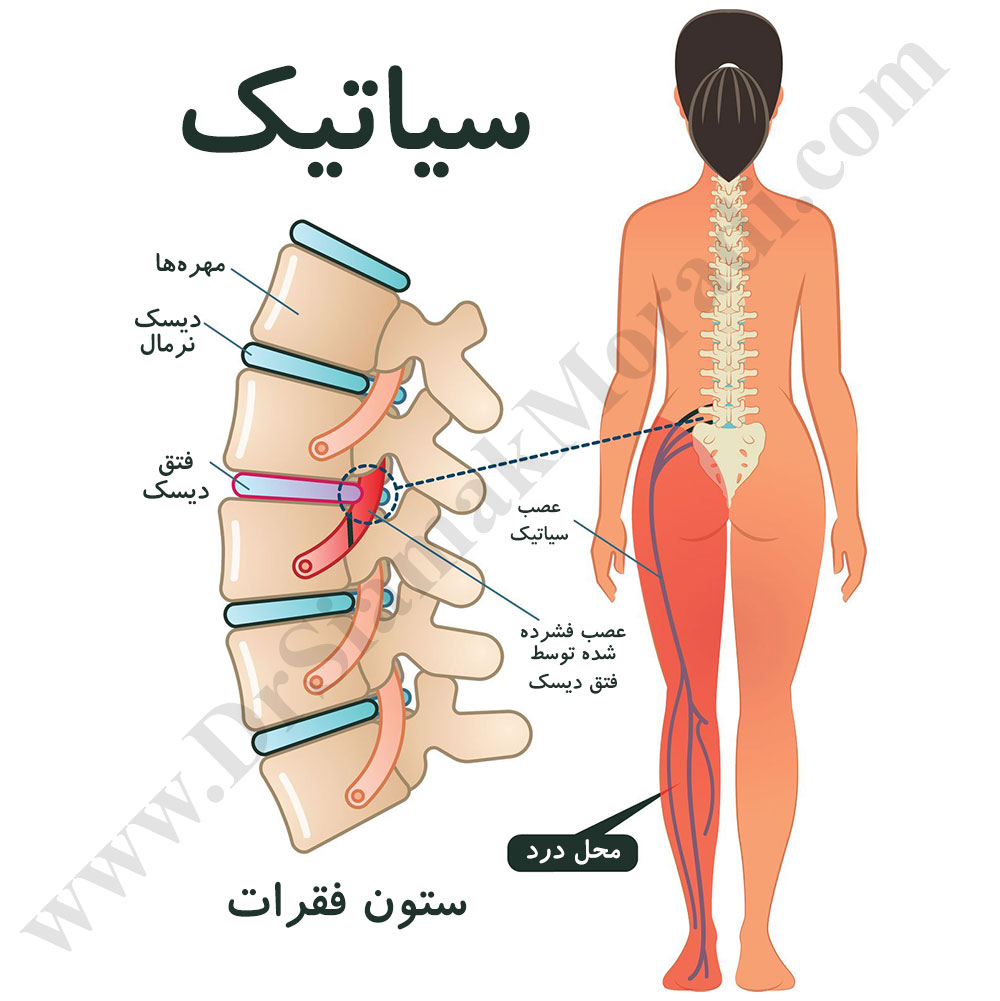

دسته بندی مقالات : سیاتیک

علت و درمان عصب سیاتیک کمر

درمان سیاتیک برای همیشه: درمان درد سیاتیک پای راست و پای چپ چیست